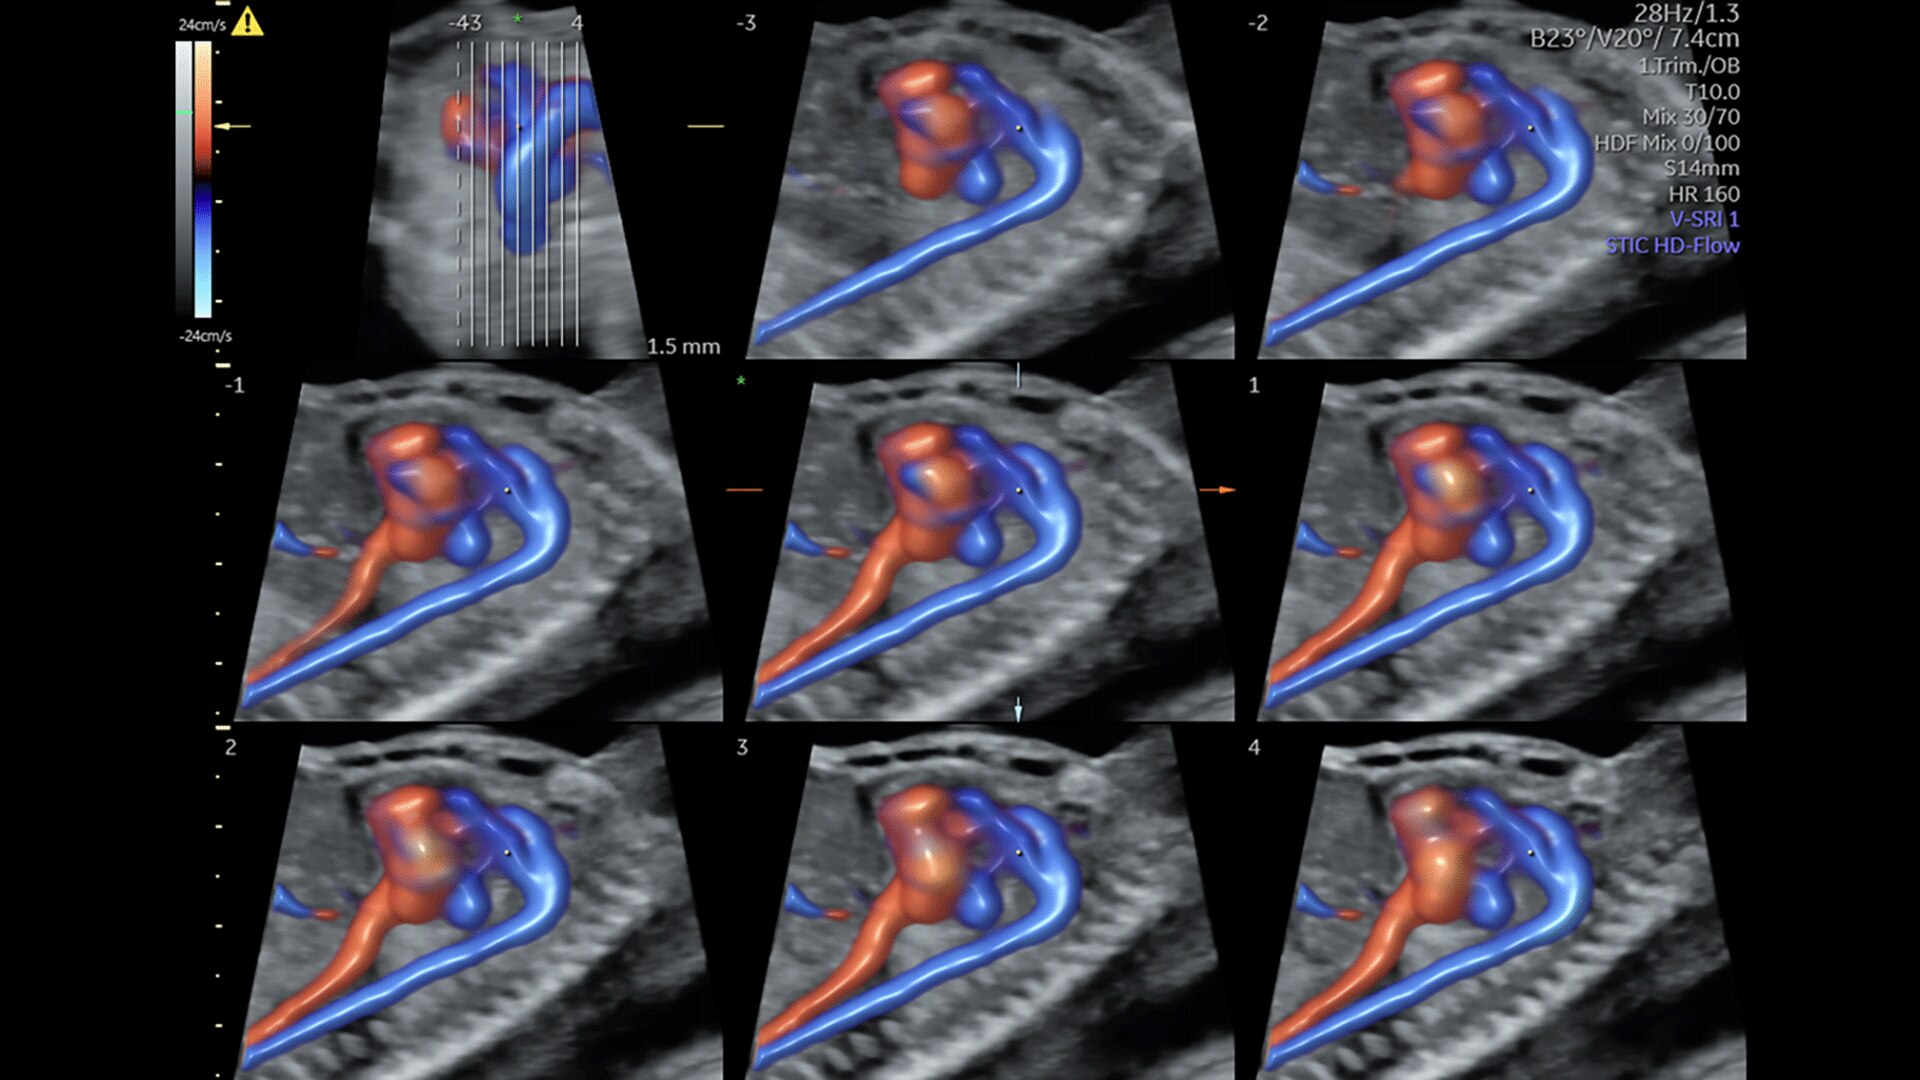

FETAL HEART EVALUATION

Get to the Heart of the Matter

Identifying fetal cardiac abnormalities earlier means you can intervene sooner, plan for delivery, and potentially improve outcomes. The Voluson Expert 22 provides a full solution of progressive tools, to help distinguish the tiniest structures with stunning clarity to provide patient answers faster.